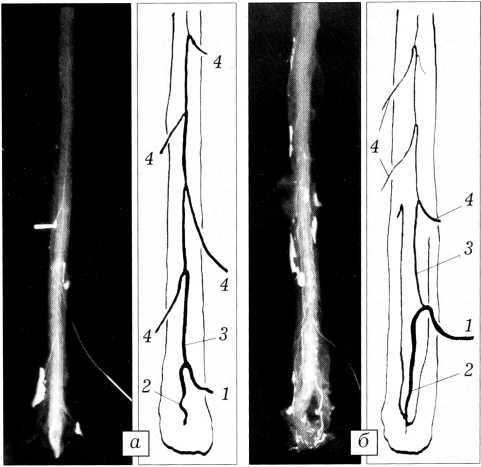

Все исследованные препараты были разделены нами согласно классификации А.А. Скоромца [1- 3], в которой выделяются магистральный тип кровоснабжения передней спинальной артерии (варианты 1,2,3) и рассыпной тип (вариант 4). Магистральный тип, вариант 1 — все сегменты спинного мозга ниже Т2-ТЗ снабжаются одной большой радикуломедуллярной артерией — артерией Адамкевича (рис. 1). Магистральный тип, вариант 2 — помимо артерии Адамкевича, имеется еще одна дополнительная радикуломедуллярная артерия, следующая со вторым поясничным или первым крестцовым корешком. Магистральный тип, вариант 3 — помимо артерии Адамкевича, имеется еще одна артерия, сопровождающая один из грудных корешков (так называемая верхняя дополнительная радикуломедуллярная артерия). Рассыпной тип (вариант 4) — грудопоясничный отдел спинного мозга кровоснабжается тремя и более радикуломедуллярными артериями, из которых одна, с большим, чем все остальные, диаметром является артерией Адамкевича (рис. 2).

Рис. 2. Рассыпной тип кровоснабжения спинного мозга: а — с равномерным, б — с неравномерным расположением дополнительных радикуломедуллярных артерий. 4 — дополнительная радикуломедуллярная артерия (остальные обозначения те же, что на рис. 1).